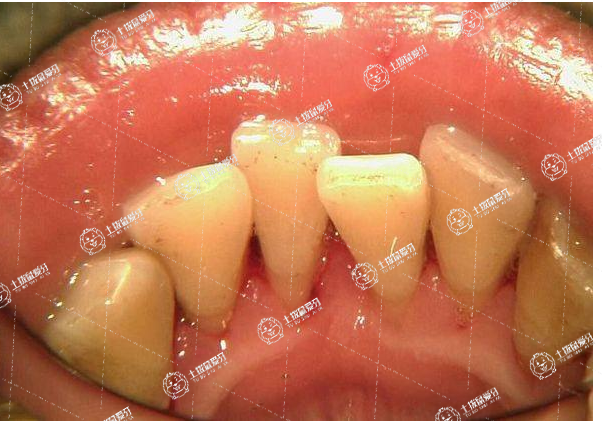

牙列擁擠臨床表現(xiàn)為不對(duì)稱的唇部外突、口腔內(nèi)牙齒參差不齊、咬合不良以及牙周創(chuàng)傷等。牙列擁擠矯正,必須根據(jù)擁擠程度、患者年齡、健康狀況以及面頜發(fā)育、面部肌肉張力等,做出正確矯正方案。

臨床上將牙齒擁擠分為輕度擁擠和重度擁擠兩種。對(duì)輕度牙齒擁擠的矯正,擁擠程度表現(xiàn)為上下切牙扭轉(zhuǎn)錯(cuò)位,或尖牙輕度唇向錯(cuò)位,采用牙套正畸矯正方法。中度和重度擁擠,采用重塑拔牙配合矯正器治療。成年人生長(zhǎng)發(fā)育已經(jīng)完成,代謝速率變慢、生物反應(yīng)性降低,采用正畸矯正成人牙列擁擠或比兒童所花時(shí)間更長(zhǎng)些。牙列擁擠可通過拔牙或不拔牙方式進(jìn)行矯正。